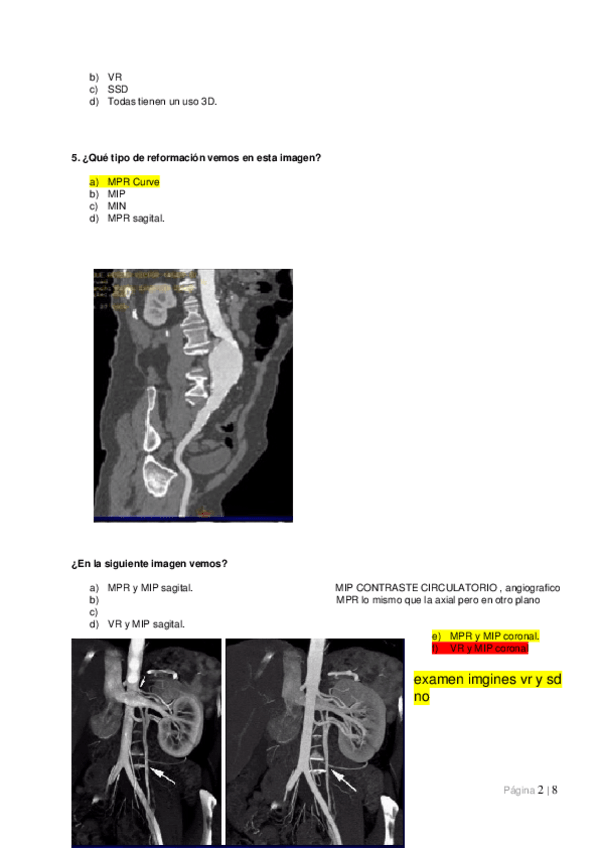

Unidades Hounsfield, ventanas, parámetros de calidad de la imagen, artefactos y reconstrucciones.